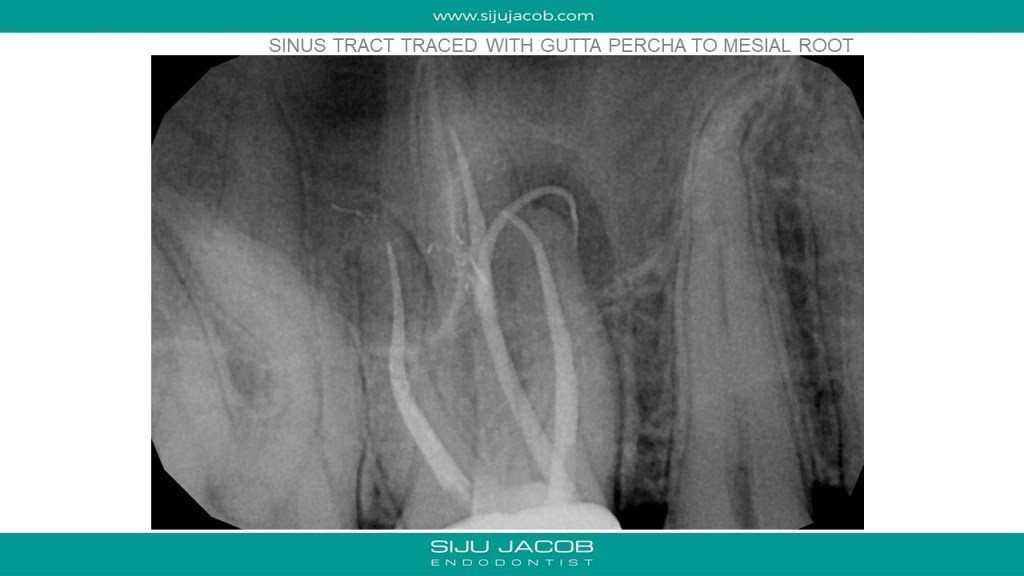

Re-treatment due to missed Mb2 is probably the most commonly referred procedure that I do. And almost every time, I leave the other canals alone. in this case, the referral did endo and placed a new crown, after which the patient had pain followed by a sinus tract. G.p cone tracing of the sinus tract led to the mesial root. We managed to do this with the very conservative opening, thereby preserving the new crown. (in hindsight, i probably should have left the mb1 alone)